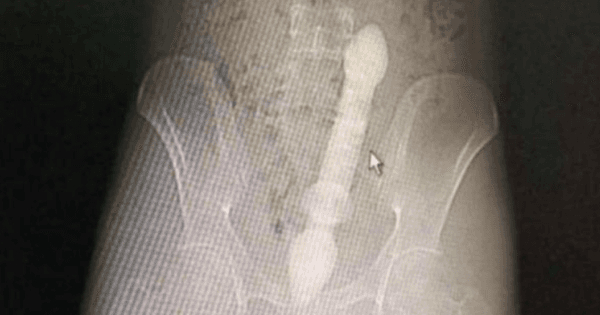

Man Who Shoved A 20cm-Long Sex Toy Up His Anus Says He Did It For Fun

The incident happened on 1 January.